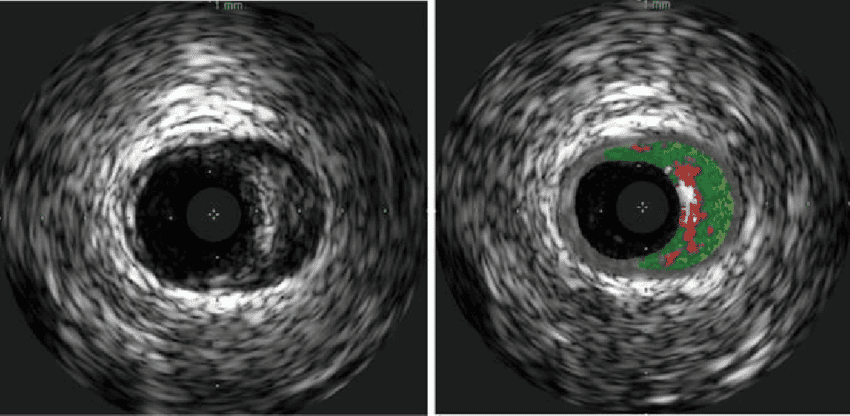

Siêu âm trong lòng mạch là kỹ thuật siêu âm sử dụng ống thông đặc biệt nhằm quan sát, đánh giá hình ảnh cấu trúc mạch máu. Một đầu của ống thông được gắn vào đầu dò phát sóng siêu âm, đầu còn lại được kết nối với hệ thống máy ghi nhận và xử lý hình ảnh. Ống thông sẽ được luồn qua một dây dẫn thẳng vào trong lòng mạch máu, đến vị trí cần khảo sát và ghi lại hình ảnh mạch máu. Thông qua hình ảnh thu được, các bác sĩ sẽ đánh giá tình trạng mạch máu và chẩn đoán các bệnh lý liên quan.

Siêu âm trong lòng mạch là phương pháp chẩn đoán hình ảnh được áp dụng trong các trường hợp nghi ngờ có bệnh lý về mạch máu, nhất là bệnh lý về động mạch vành. Kết quả thu được từ siêu âm trong lòng mạch phản ánh chi tiết, cụ thể tình trạng mạch máu, bao gồm: kích thước, hình dạng, các tổn thương xơ vữa mạch, vôi hóa, huyết khối… Do đó trong các trường hợp khó xác định bệnh động mạch vành thì ngoài việc chụp mạch vành thông thường, bác sĩ thường chỉ định siêu âm trong lòng mạch kết hợp để có kết quả chẩn đoán chính xác.

Ống thông IVUS là một ống mỏng. Một đầu của ống gắn vào đầu dò siêu âm, đầu còn lại kết nối với máy tính để truyền tín hiệu từ đầu dò thành hình ảnh trên màn hình. Siêu âm trong lòng mạch giống các kỹ thuật siêu âm khác, cũng sử dụng sóng âm thanh tần số cao để ghi lại hình ảnh cấu trúc mạch máu.

Tùy từng tình trạng cụ thể mà một số bệnh nhân có thể sẽ được chỉ định gây mê toàn thân, còn lại bệnh nhân sẽ được gây tê tại chỗ. Bác sĩ sẽ sát khuẩn vị trí đặt ống thông và phủ vải phẫu thuật lên trên. Một dụng cụ dẫn đường sẽ được bác sĩ luồn vào động mạch cẳng tay hoặc động mạch đùi. Ống thông được luồn vào dụng cụ dẫn đường, đi đến vị trí cần khảo sát trên một sợi dây dẫn mềm. Quá trình này được thực hiện dưới hướng dẫn của màn tăng sáng. Tại đây, sóng siêu âm sẽ tạo ra hình ảnh của cấu trúc mạch máu, phản xạ lại màn hình hiển thị.